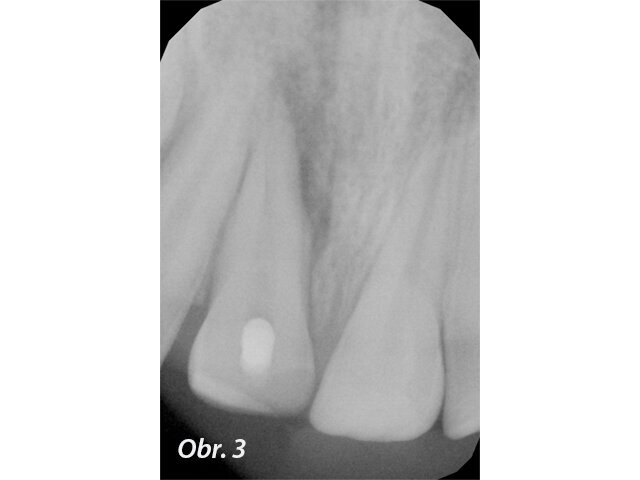

Při klinickém vyšetření nacházíme sanovaný smíšený chrup odpovídající věku pacienta. Zub 11 je poklepově a palpačně nebolestivý, parodontální sondáž je v mezích fyziologické normy. Z vestibulárního pohledu tvarově a velikostně odpovídá kontralaterálnímu zubu (obr. 1), z okluzního pohledu je vestibuloorální rozměr nepatrně větší než u zubu 21 (obr. 2). Šikmá fraktura zubu 11 má meziální okraj cca 1 mm nad okrajem marginální gingivy a distálně zasahuje do incizální třetiny klinické korunky. Dle diagnostického intraorálního rentgenového snímku je ukončen vývoj kořene s přítomným periapikálním nálezem a projasněním na meziálním aspektu kořene. Na ortoradiálním intraorálním rentgenovém snímku, ve srovnání se zubem 21 není jasně zřetelný průběh kořenového kanálku (obr. 3) a na excentrickém rentgenovém snímku je viditelný náznak kontury druhého kořene (obr. 4).